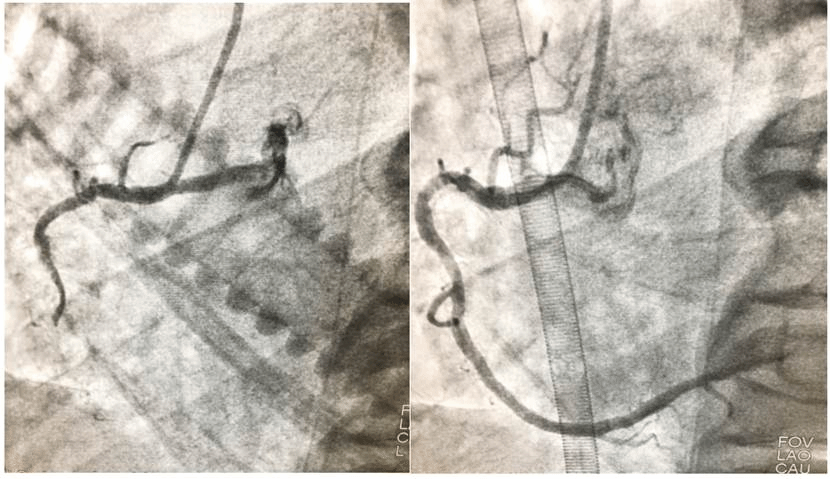

经过20分钟的抢救,在ECMO的支持下患者恢复了自主心律及血压。心内科王中华副主任医师立即为患者行冠状动脉介入治疗及IABP治疗。凌晨3时20分,成功开通患者血管!患者的生命,抢救成功了!